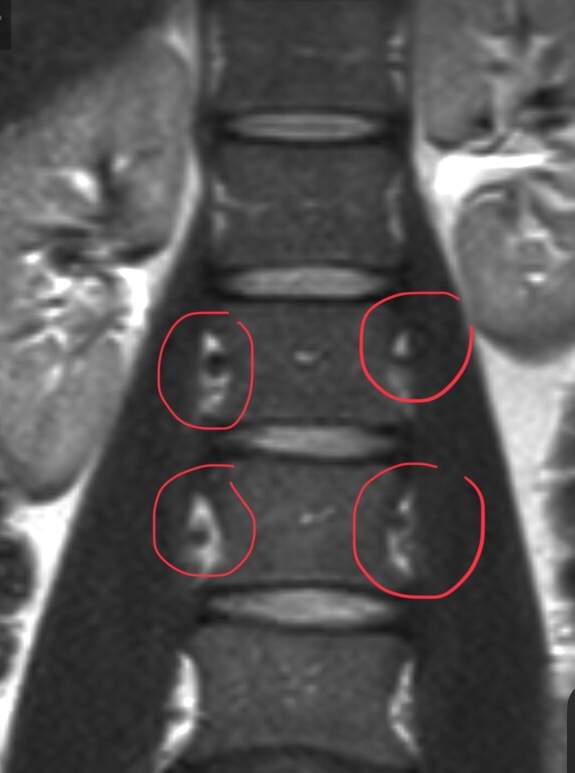

Kann Jemand Magnetresonanz Mrt Bilder Bewerten Arzt Wirbelsaule Bandscheibenvorfall